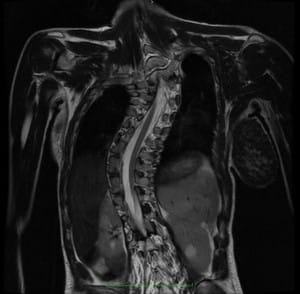

Figura 1.- Ressonància Nuclear Magnètica (RM) amb secció coronal de la columna vertebral en una Escoliosi idiopàtica, en la que es visualitza el canal vertebral amb la medul·la espinal, la qual va de convexitat a convexitat dins del canal vertebral, indicant l’existència d’una força de tracció medul·lar caudal important